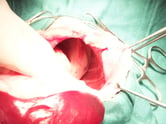

【子宮蓄膿症】

膿が貯留しているため腫大している子宮。腹腔内に膿が漏れ出ると腹膜炎を起こし重篤な状態となる。救命を第一に、卵巣・子宮全摘出を行うことが多い。